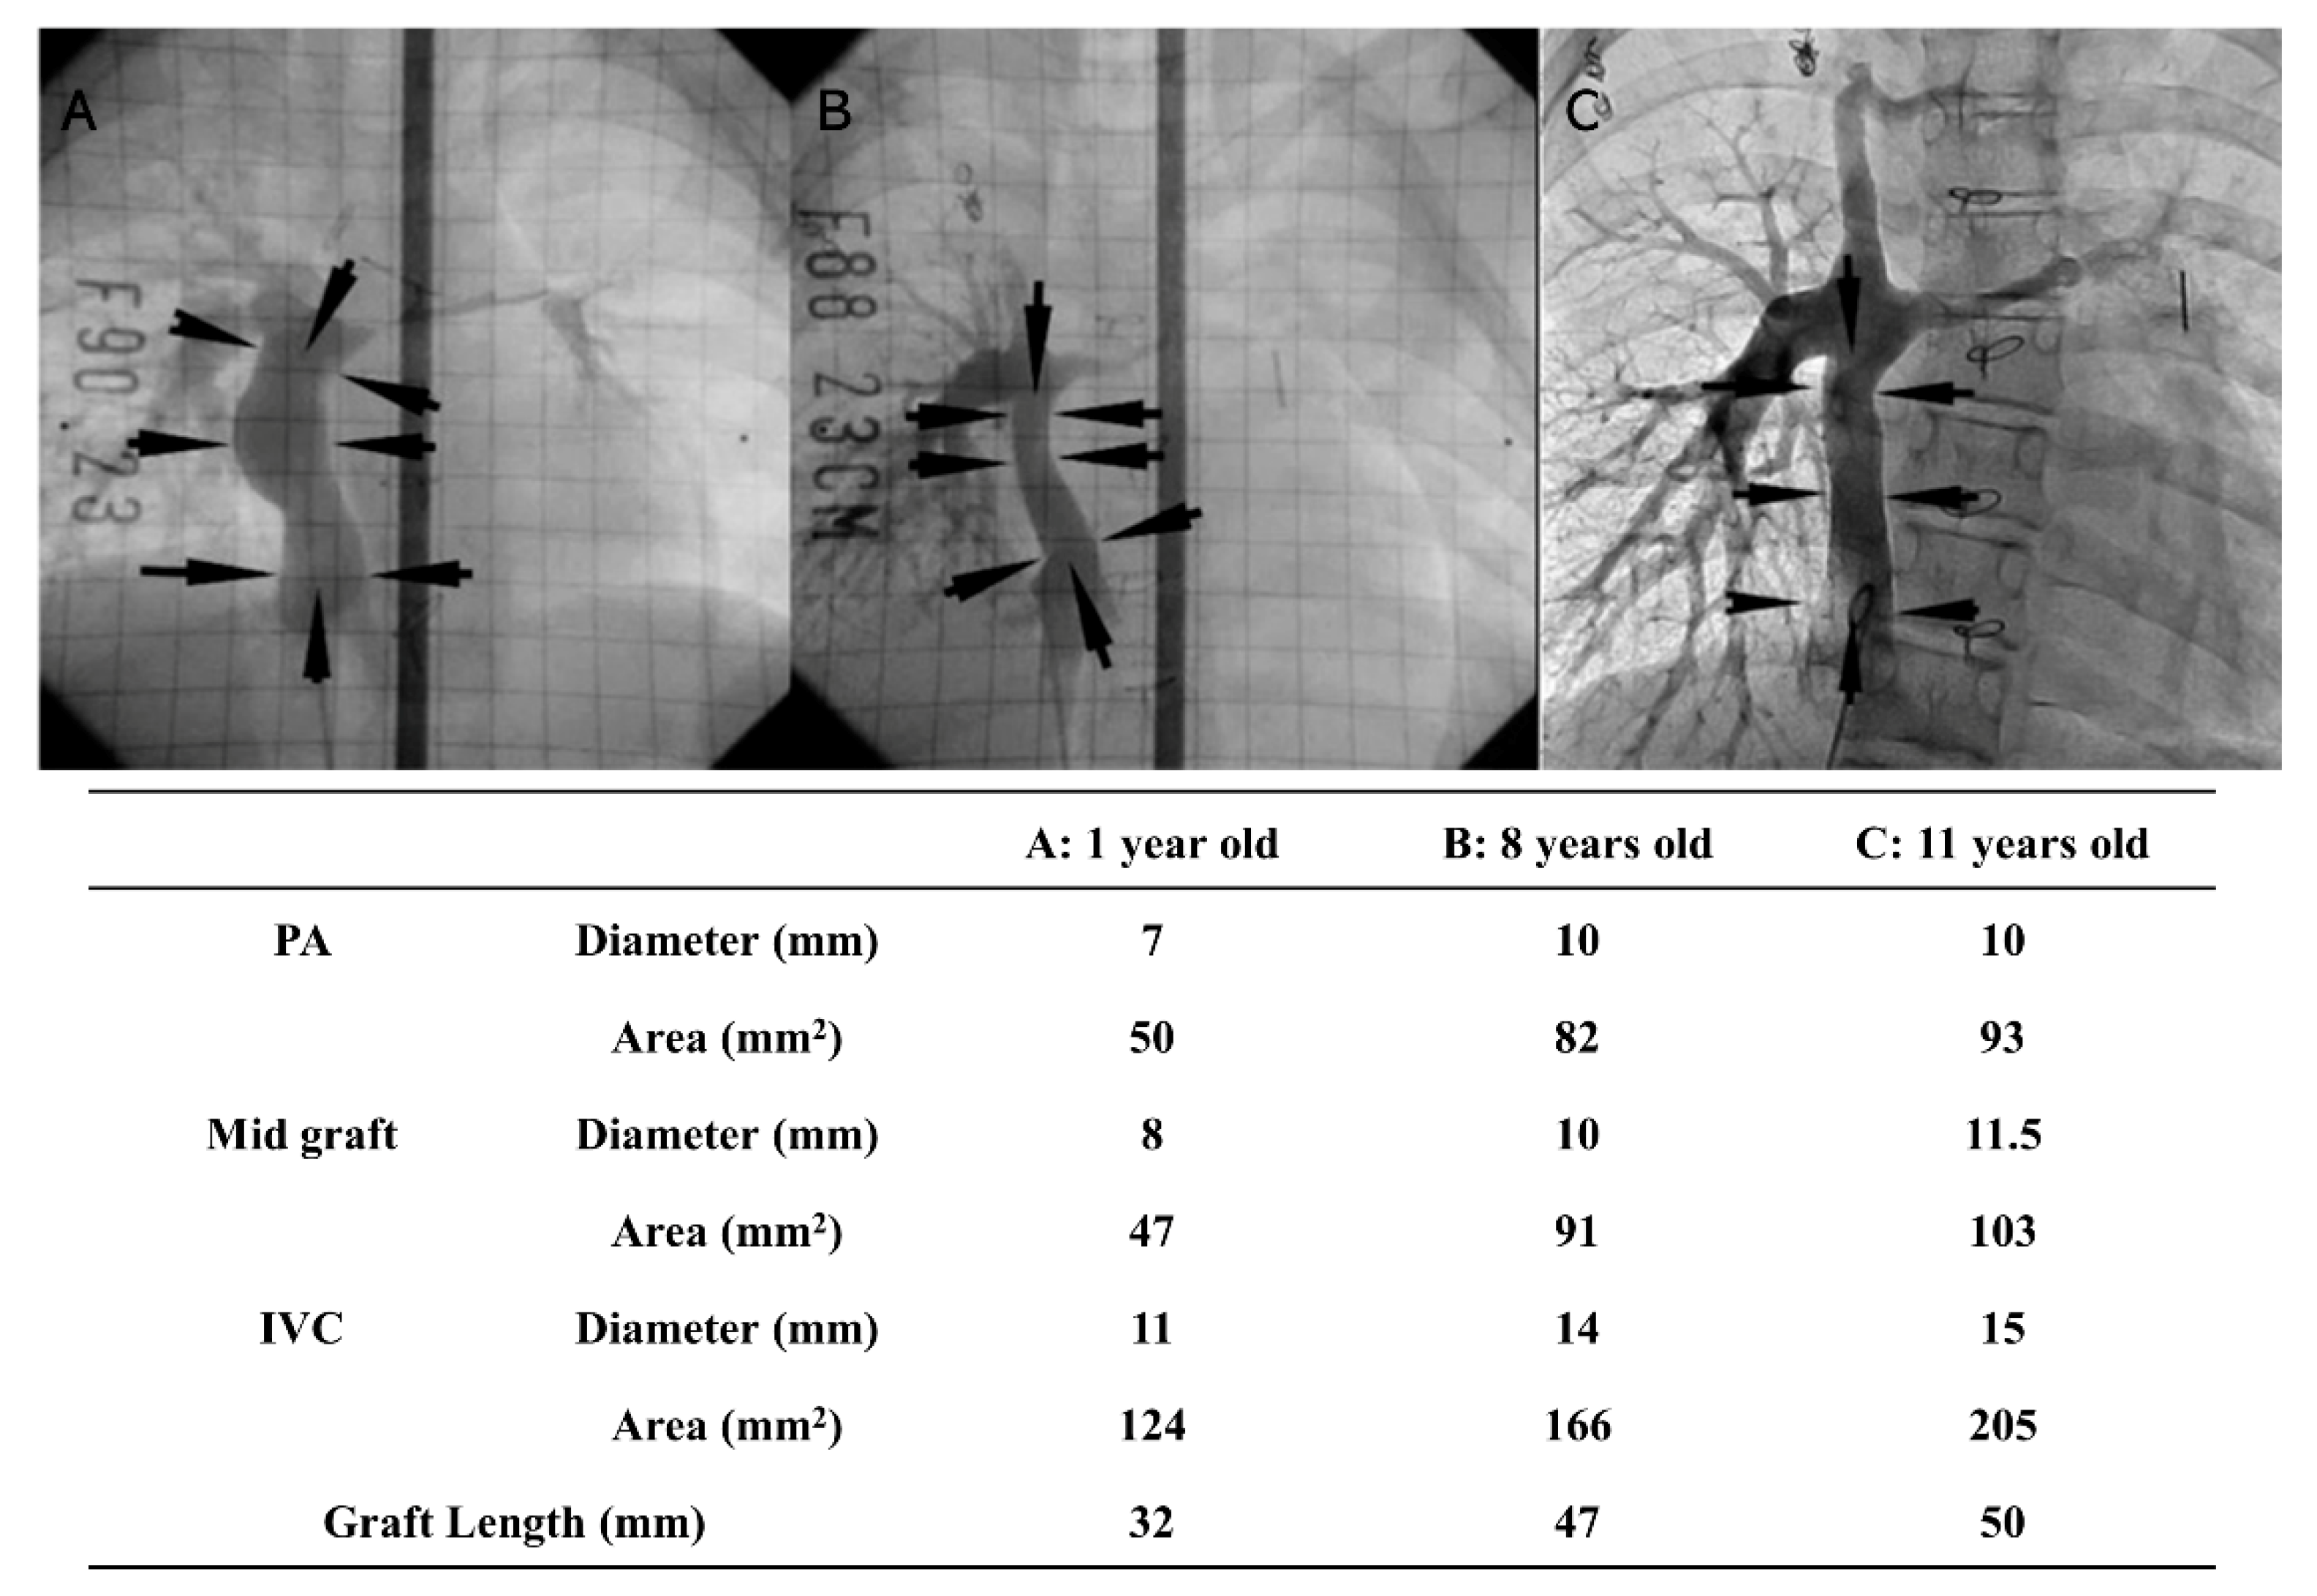

- Sugiura, T.; Matsumura, G.; Miyamoto, S.; Miyachi, H.; Breuer, C.K.; Shinoka, T. Tissue-engineered Vascular Grafts in Children With Congenital Heart Disease: Intermediate Term Follow-up. Semin. Thorac. Cardiovasc. Surg. 2018, 30, 175–179. [Google Scholar] [CrossRef] [PubMed]